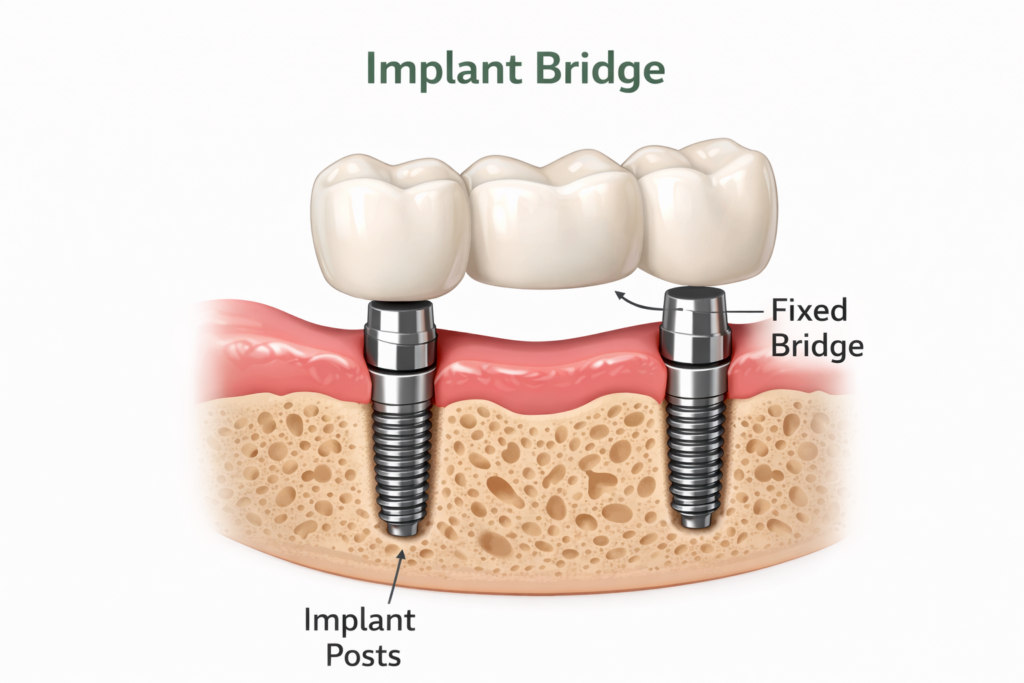

When several teeth are missing in a row, implant bridges provide a stable and supportive solution. Instead of relying on surrounding teeth, this option uses implants placed directly into the jawbone.

Implant bridges help evenly distribute bite forces, improving comfort and durability. They also support proper alignment while helping preserve healthy bone levels.